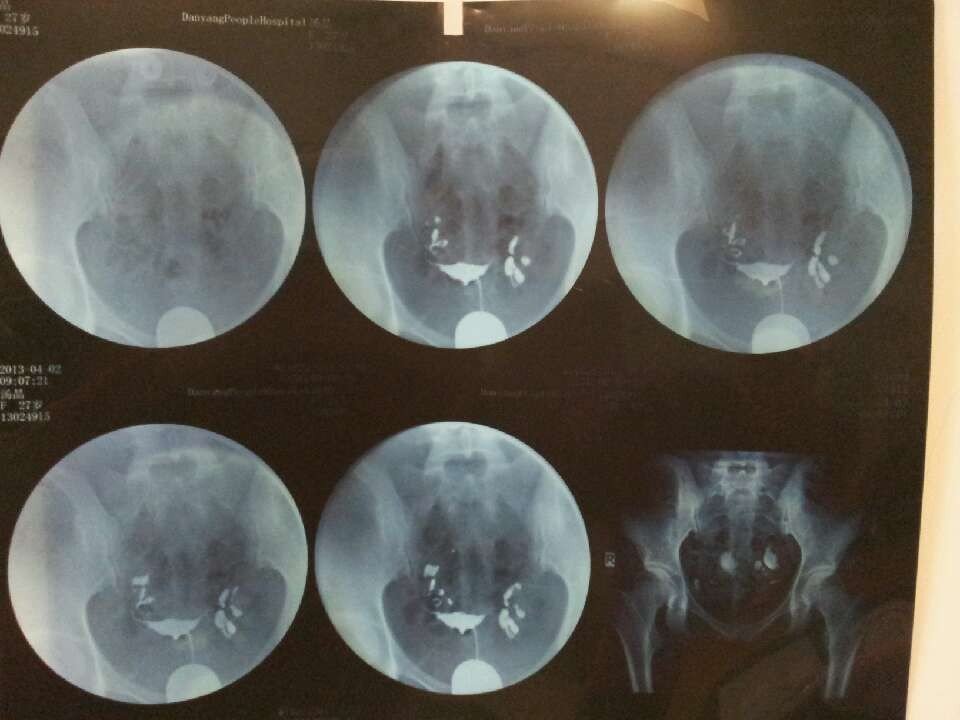

最近造影归来,子宫形态无明显异常,双侧输卵管通畅,双侧输卵管伞不显影无殊!造影剂在盆腔内弥散不佳! 请问这种情况是不是必须要腹腔镜,有别的治疗办法吗? 点击展开 匿名用户 2013-04-04 22:17 推荐回答 双侧输卵管远端扭曲扩张,延迟拍片可见造辉清影剂府眠抓聚集,考虑残灿双侧输卵管炎症,通畅性不良。 陶茹薇 2013-04-05 09:23 宝宝知道提示您:回答为网友贡献,仅供参考。 相关问题 双侧输卵管通畅,呈迂曲柔软的条状影双侧输卵管伞部显影稍成团 24小时后摄片示:造影剂在盆腔内弥散 最近造影归来,子宫形态无明显异常,双侧输卵管通畅,双侧输卵管伞不显影无殊!造影剂在盆腔内弥散不佳! 双侧输卵管近端显影良好,壁管柔软,远端均扭曲稍增粗,双侧造影游离畅顺,盆腔内见造影剂弥散,诊断和建